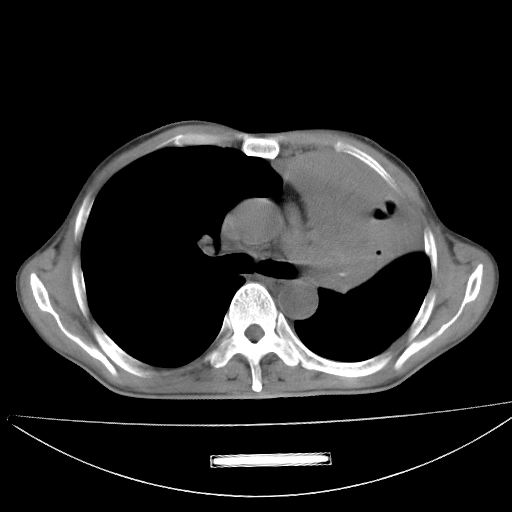

以下是引用杀毒软件在2009-4-28 17:58:00的发言:[br]考虑----左肺慢性肺脓肿形成继发上叶含气不良---抗炎后复查---待排肿瘤所致[br][br][本贴已被 杀毒软件 于 2009-4-28 18:01:26 修改过]